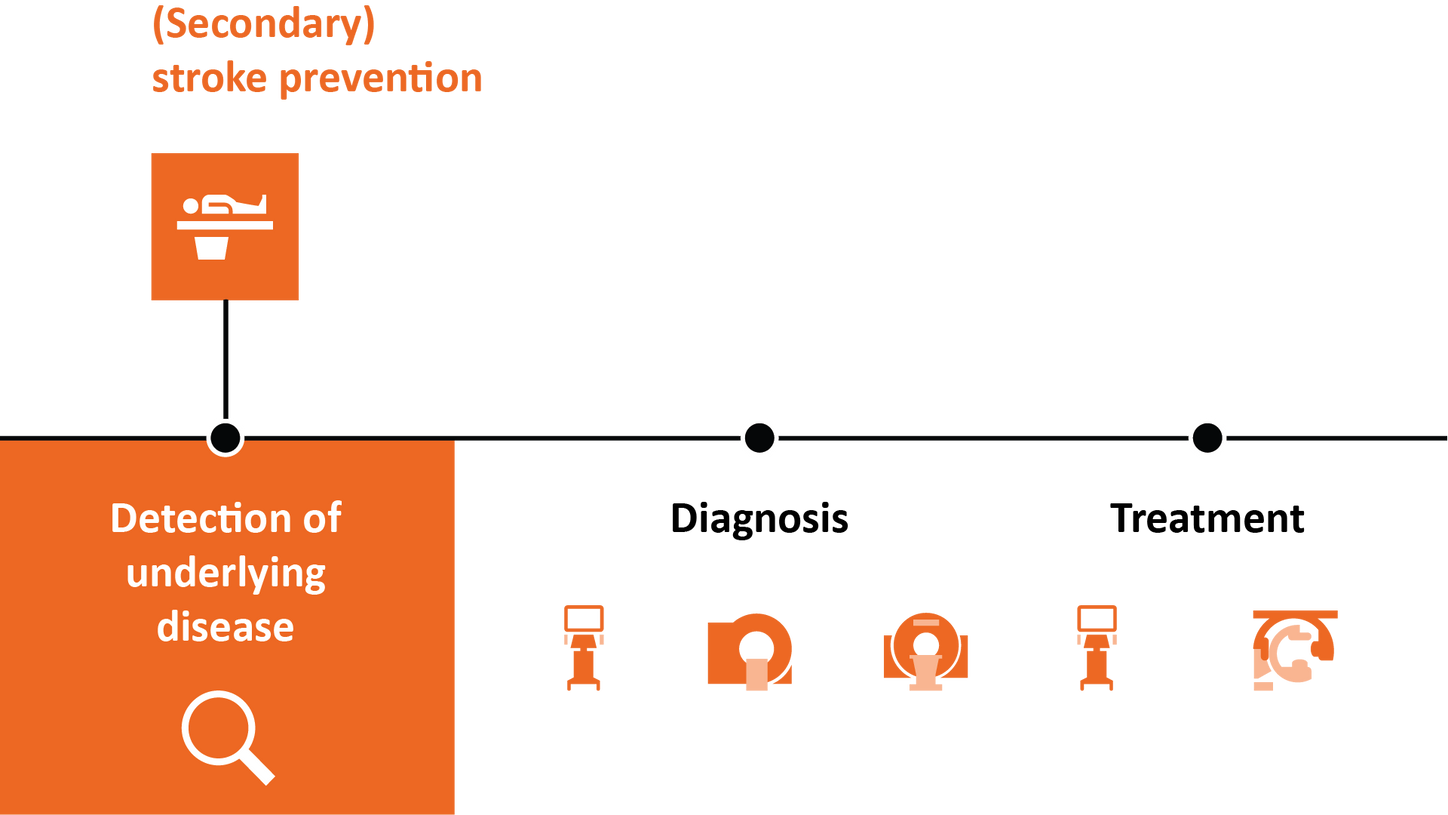

Stroke solutions

As your partner in stroke management, we keep you ahead of your time. Our advanced technologies let you speed up stroke care and transform care delivery along the entire pathway – from stroke screening and pre-hospital diagnosis and care to in-hospital diagnosis and treatment and (secondary) stroke prevention to follow-up imaging. Explore our offerings for stroke care!

The WAKE-UP trial shows favorable outcomes for acute ischemic stroke patients with an unknown stroke onset: Patients identified by DWI-FLAIR mismatch on MRI with subsequent thrombolysis had significantly better functional outcomes than the placebo group.7

The DAWN trial shows that time alone shouldn’t be a disqualifier for endovascular thrombectomy. For example: 48.6% of patients in the thrombectomy group experienced less disability, compared to 13% in the control group who received standard medical care.4

DEFUSE 3 shows favorable outcomes for late-window patients. For example: Mortality rate was 14% in the endovascular therapy group, compared to 26% in the medical therapy group. And there was no significant between-group difference in adverse events.4

ESCAPE trial “Among patients with acute ischemic stroke with a proximal vessel occlusion, a small infarct core, and moderate-to-good collateral circulation, rapid endovascular treatment improved functional outcomes and reduced mortality.” (from the publication)5